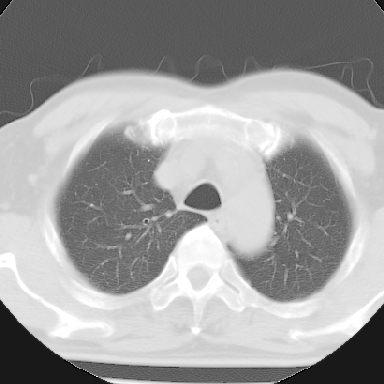

标题: CT8275:M 77 反复咳嗽咳痰10多年,慢性支气管炎请分析 [打印本页]

标题: CT8275:M 77 反复咳嗽咳痰10多年,慢性支气管炎请分析

m 77 反复咳嗽咳痰10多年,再发加重4天

纵隔窗呢?慢支炎肺气肿;余未见明显渗出及占位!

慢性支气管炎、肺气肿。

这份病例诊断慢支并气肿可能属过诊,首先慢支的临床诊断标准是严格的,应该弄清楚,其次ct表现是否符合该病表现,本例老年人ct肺窗表现应属正常,不要跟着临床跑。